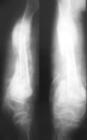

根據病史和臨床表現,診斷不難。特別是有竇道及經竇道排出過死骨時,診斷更易。攝X線片可以證實有無死骨,並了解其形狀、數量、大小和部位,以及附近包殼的生長情況。一般病例不需要做CT檢查,因骨質濃白難以顯示死骨者可做CT檢查。

慢性血源性骨髓炎早期階段有蟲蛀狀骨破壞與骨質稀疏,並逐漸出現硬化區。骨膜掀起並有新生骨形成,骨膜反應為層狀,部分呈三角狀,狀如骨腫瘤。新生骨逐漸變厚和緻密,壞死脫落成為死骨。由於周圍骨質緻密,死骨在常規正、側位X線片上可能不能被顯示,需要改變體位檢查,在X線片上,死骨表現為完全孤立的骨片,沒有骨小梁結構,濃白緻密,邊緣不規則,周圍有空隙,CT片可以顯示出膿腔與小型死骨,在部分病例可經竇道插管注入碘水造影劑以顯示膿腔。